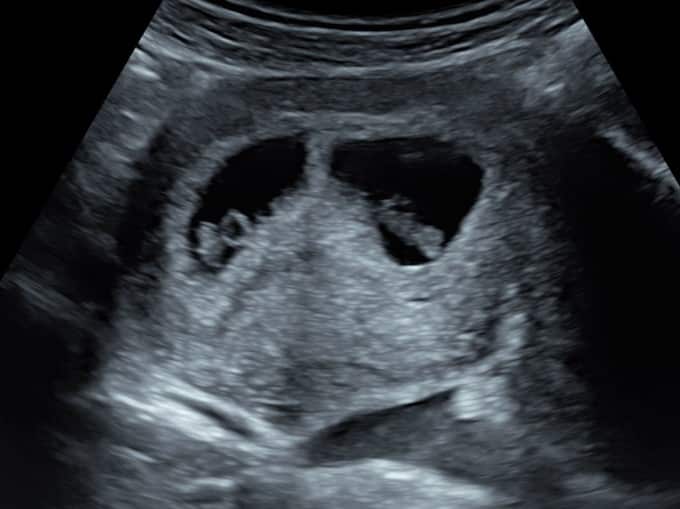

At 6 weeks, baby is only around 4mm so is very small. You’ll see a pregnancy sac, a yolk sac (which provides baby with all the nutrients they need until the placenta takes over, around week 10) and baby’s heartbeat.

The first thing the sonographer looks for is the position of baby. They will check the baby is in the uterus as it should be, rather than elsewhere which can be dangerous for mum. The sonographer will then look for the number of pregnancy sacs and babies to confirm a single or multiple pregnancy. The heartbeat is next; during your early pregnancy scan we do not listen to the heartbeat as it wouldn’t be safe for baby, but we will show you the heartbeat flickering on our screens.

Once the pelvic assessment is complete, the sonographer will return to your baby and measure their length from crown to rump (head to tail) to provide you with accurate dating.